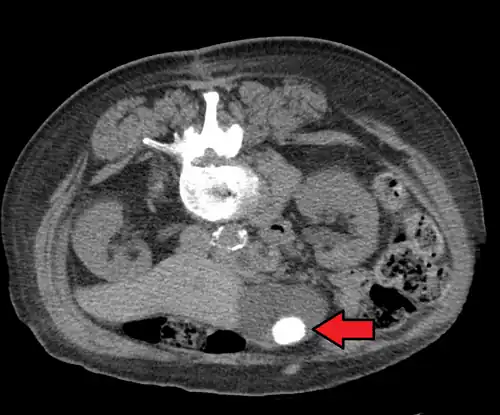

Choledocholithiasis

Choledocholithiasis refers to a gallstone obstructing the common bile duct.[20] Patients typically experience right upper quadrant pain, back pain, jaundice (or yellowing of the skin), decreased appetite, nausea, vomiting, and fever.[13][20] However, choledocholithiasis, just like gallstones, can also be asymptomatic.[14][21] If the patient has symptoms, the physical exam is similar to that of acute cholecystitis.[20] Laboratory studies show an increase in direct (conjugated) bilirubin, gamma-glutamyl transpeptidase (GGT), and alkaline phosphatase. AST and ALT can be elevated or normal.[14][15][21]